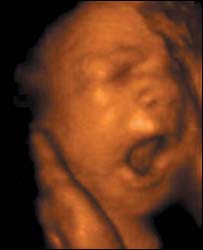

جنس کی تشخیص فائل فوٹو

ہندوستان میں رحم مادر میں جنس کی تشخص پر پابندی عائد ہے لیکن اس باوجود خاطر خواہ تبدیلی نہيں آئی ہے کیونکہ والدین لڑکوں کو لڑکیوں پر ترجیح دیتے ہیں۔